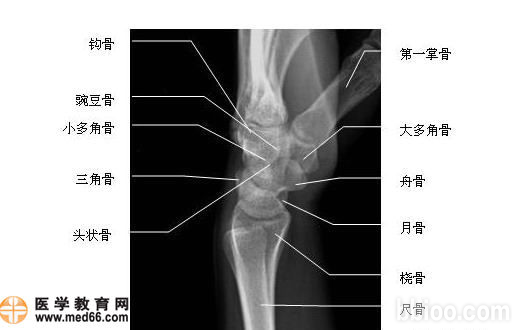

正常腕关节

腕关节

桡腕关节

腕掌关节

腕关节解剖

腕关节解剖图

腕关节正侧位